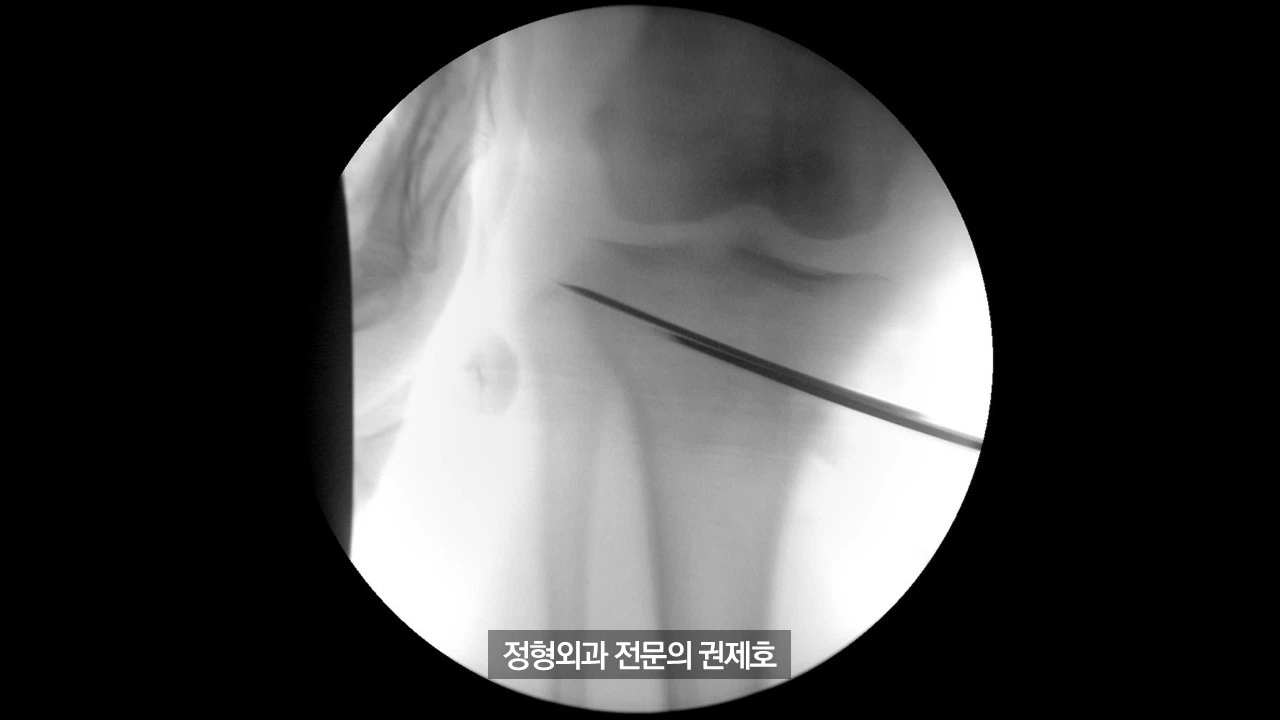

간이 엑스레이 기기를 통해 촬영한 사진이며 (좌측) 가이드 핀을 이용해서 절골할 길을 만드게 되고, (우측) 절골도를 이용하여 천천히 절골을 시행하게 됩니다.